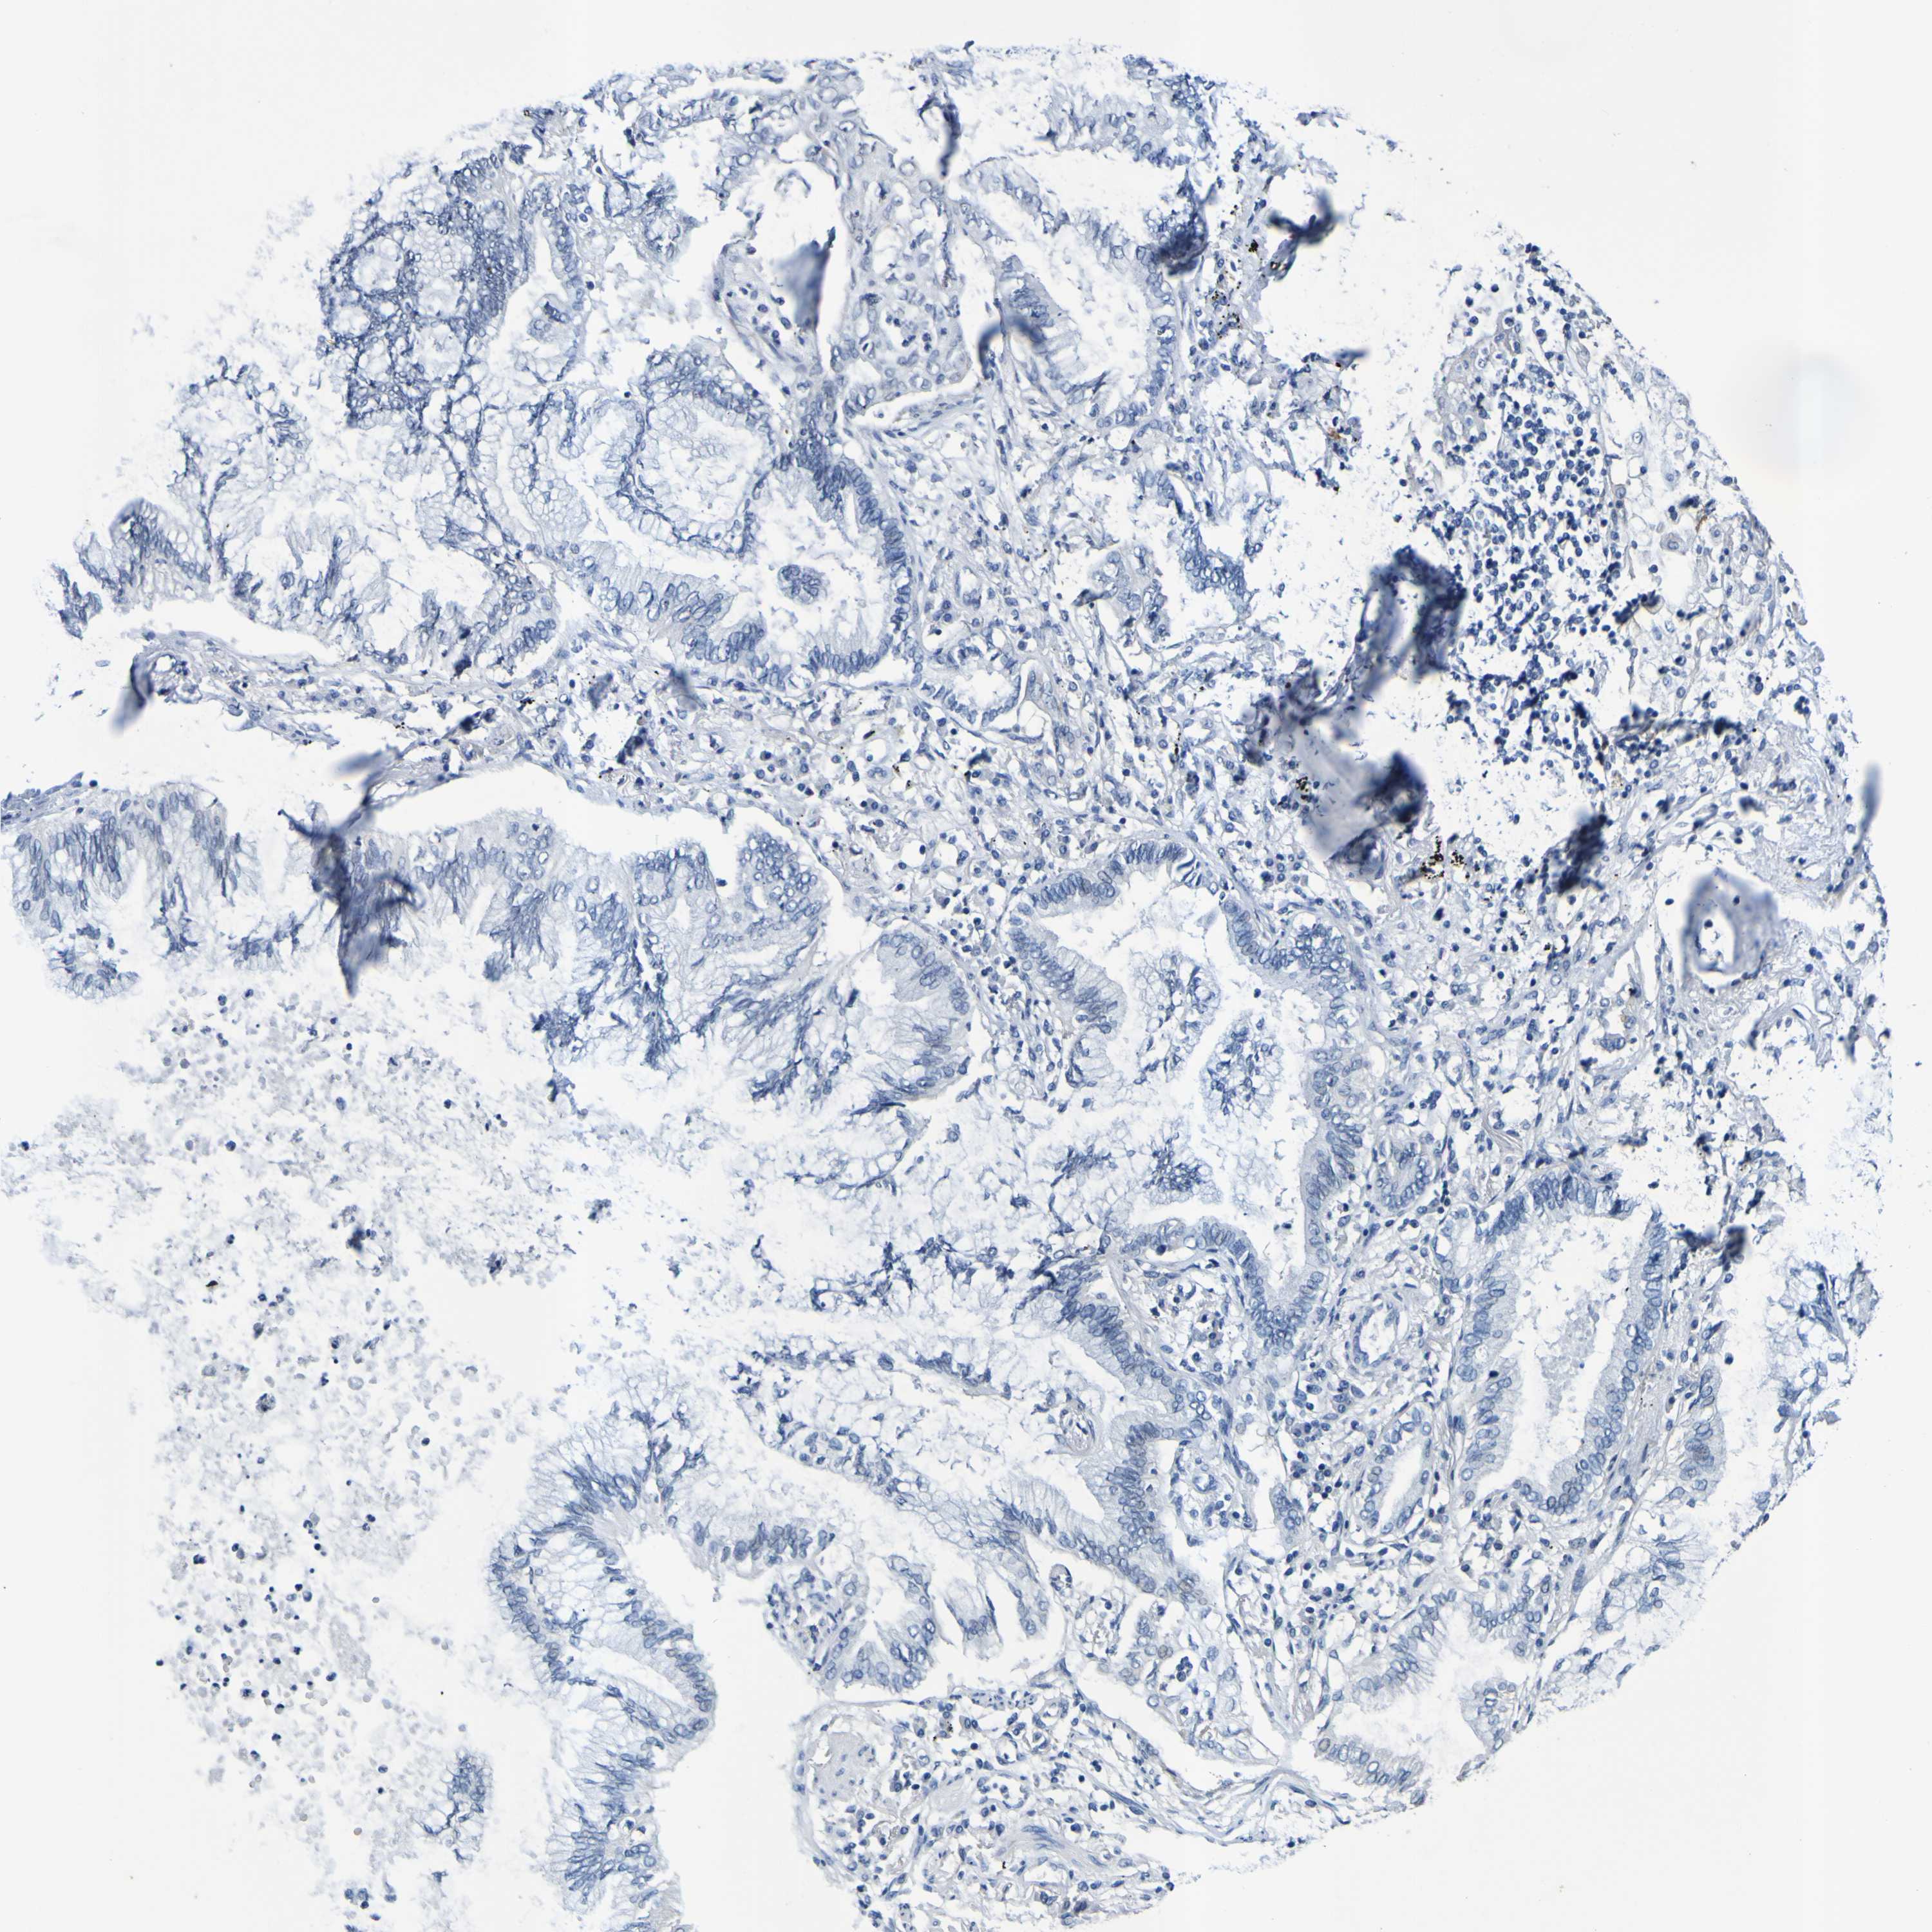

CANCER LUNG CANCER Show tissue menu

LUAD TCGA LUAD VALIDATION LUSC TCGA LUSC VALIDATION PROTEIN LUAD CPTAC PROTEIN LUSC CPTAC PROTEIN EXPRESSION

LUNG ADENOCARCINOMA (TCGA) - Interactive survival scatter ploti

The Survival Scatter plot shows the clinical status (i.e. dead or alive) for all individuals in the patient cohort, based on the same data that underlies the corresponding Kaplan-Meier plots. Patients that are alive at last time for follow-up are shown in blue and patients who have died during the study are shown in red.

The x-axis shows the expression levels (FPKM) of the investigated gene in the tumor tissue at the time of diagnosis. The y-axis shows the follow-up time after diagnosis (years). Both axes are complimented with kernel density curves demonstrating the data density over the axes. The top density plot shows the expression levels (FPKM) distribution among dead (red) and alive patients (blue). The right density plot shows the data density of the survived years of dead patients with high and low expression levels respectively, stratified using the cutoff indicated by the vertical dashed line through the Survival Scatter plot. This cutoff is automatically defined based on the FPKM cutoff that minimizes the p-score. The cutoff can be changed by dragging the vertical line or by entering a cutoff value in the square labeled "Current cut-off".

Under the Survival Scatter plot the p-score landscape (black curve; left axis) is shown together with dead median separation (red curve; right axis). Dead median separation is the difference in median mRNA expression between patients who have died with high and low expression, respectively. It is calculated as follows: median FPKM expression of dead patients with high expression - median FPKM expression of dead patients with low expression. This is intended to aid the user in visually exploring custom cutoffs and the associated p-scores and dead median separation.

Individual patient data is displayed and can be filtered by clicking on one or more of the category buttons on the top of the page. Categories describing expression level and patient information include: high, low, alive, dead, female, male and tumor stages. The scale of the x-axis can be toggled between linear and log-scale by clicking on the "x log" button. Mouse-over function shows TCGA ID, patient information and mRNA expression (FPKM) for each patient.

& Survival analysisi

Kaplan-Meier plots summarize results from analysis of correlation between mRNA expression level and patient survival. Patients were divided based on level of expression into one of the two groups "low" (under cut off) or "high" (over cut off). X-axis shows time for survival (years) and y-axis shows the probability of survival, where 1.0 corresponds to 100 percent.

VMA21 is not prognostic in Lung Adenocarcinoma (TCGA)

Best expression cut offi

: 15.97

P scorei

N/A

5-year survival highi

5-year survival lowi

TCGA RNA samplesi

RNA-seq data is reported as average FPKM (number Fragments Per Kilobase of exon per Million reads), generated by the The Cancer Genome Atlas (TCGA) .

Normal distribution across the dataset is visualized with box plots, shown as median and 25th and 75th percentiles. Points are displayed as outliers if they are above or below 1.5 times the interquartile range. FPKM values of the individual samples are presented next to the box plot.

Average pTPM 16.4

Number of samples 497